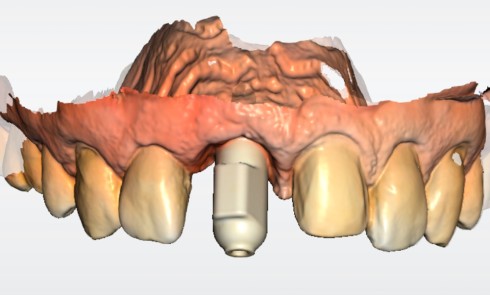

L’implant

- Péri-implantite sur l’implant 47, diagnostiquée en août 2022

- Implant posé en 2017

- Nobel Replace Select RP (4,1 x 10 mm)